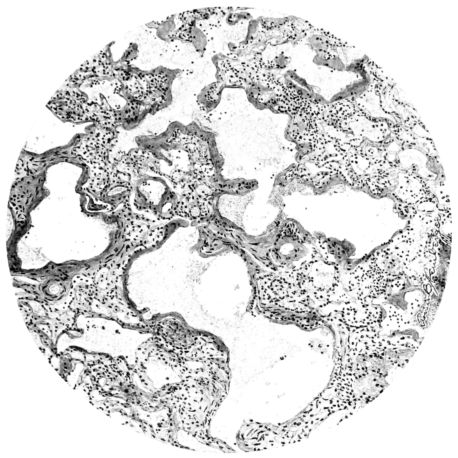

FIG. I. AUTOPSY NO. 99. ACUTE HEMORRHAGIC AND ULCERATIVE LARYNGOTRACHEITIS.

FIG. I. AUTOPSY NO. 99. ACUTE HEMORRHAGIC AND ULCERATIVE LARYNGOTRACHEITIS.

Early in the disease the congestion and the hemorrhages that have been described in the mucous membrane of the nasopharynx (14 and 94) are also conspicuous features in the lining of the trachea and bronchi (Fig. I). This membrane is swollen, turgid, red, and covered by a copious, mucous exudate which may be clear, but much more frequently is blood-stained or opaque and yellowish in color. The blood, variable in amount, may be fresh and red; and after the mucous exudate on the surface is removed, more intense red foci stand out on the congested base (47, 90, 157). Frequently, as the bronchi are approached, the red color of the mucosa becomes more intense and may have a garnet tinge. Membranes such as are encountered in the more usual necrotizing inflammatory processes, like diphtheria, have not occurred in the trachea and larger bronchi in this series (108, 128, 157).[3] The exudate peels off readily, and as indicated above, leaves a velvety red surface, 14dotted here and there with darker or more intensely red foci. Small ulcerations of the mucosa occur, but are inconspicuous (82, 156). As the finer ramifications of the bronchi are approached, the accumulation of the exudate in their lumina becomes more and more marked, and on cross section of the lung, they often stand out conspicuously on account of their increased size and projecting, seromucous, blood-stained content (101, 149, 162).